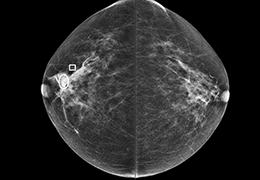

成像智能。

Eclipse 成像智能功能提供强大的处理能力和最佳质量的影像,同时减少质量错误并提高剂量效率。

凭借 AI、专有算法和先进的影像处理能力,提供出色的影像质量和无与伦比的诊断信心。

提供相配视图选项,以减少所需的曝光次数,并提供更清晰的感兴趣区域视图。